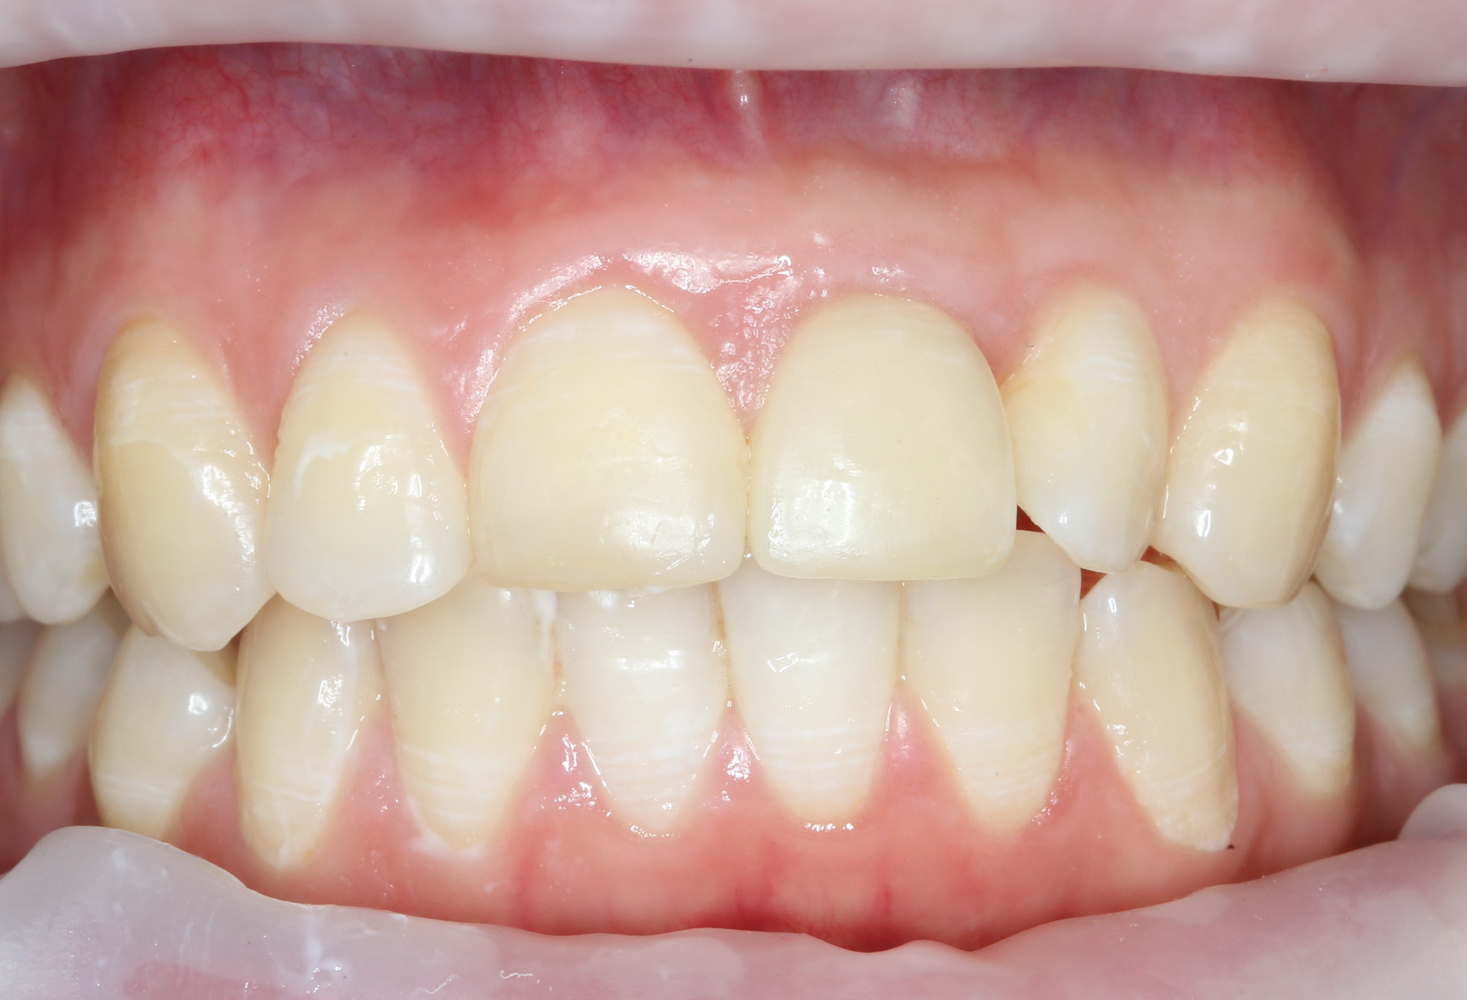

Через несколько месяцев после формирования десны, ортопед изготовил постоянную коронку:

И, на мой взгляд, получилось это очень неплохо. Сравните с тем, что было «до-«:

Наша пациентка это знает, поэтому через год заглянула к нам в клинику. И вот, что мы увидели:

На мой взгляд, это — уже хоть какой-то результат лечения. И, по мнению пациентки, с поставленной задачей мы справились.

Ей лишь остается поддерживать должный уровень гигиены, периодически посещать профилактические осмотры и, в следующий раз, быть осторожнее, катаясь на коньках.